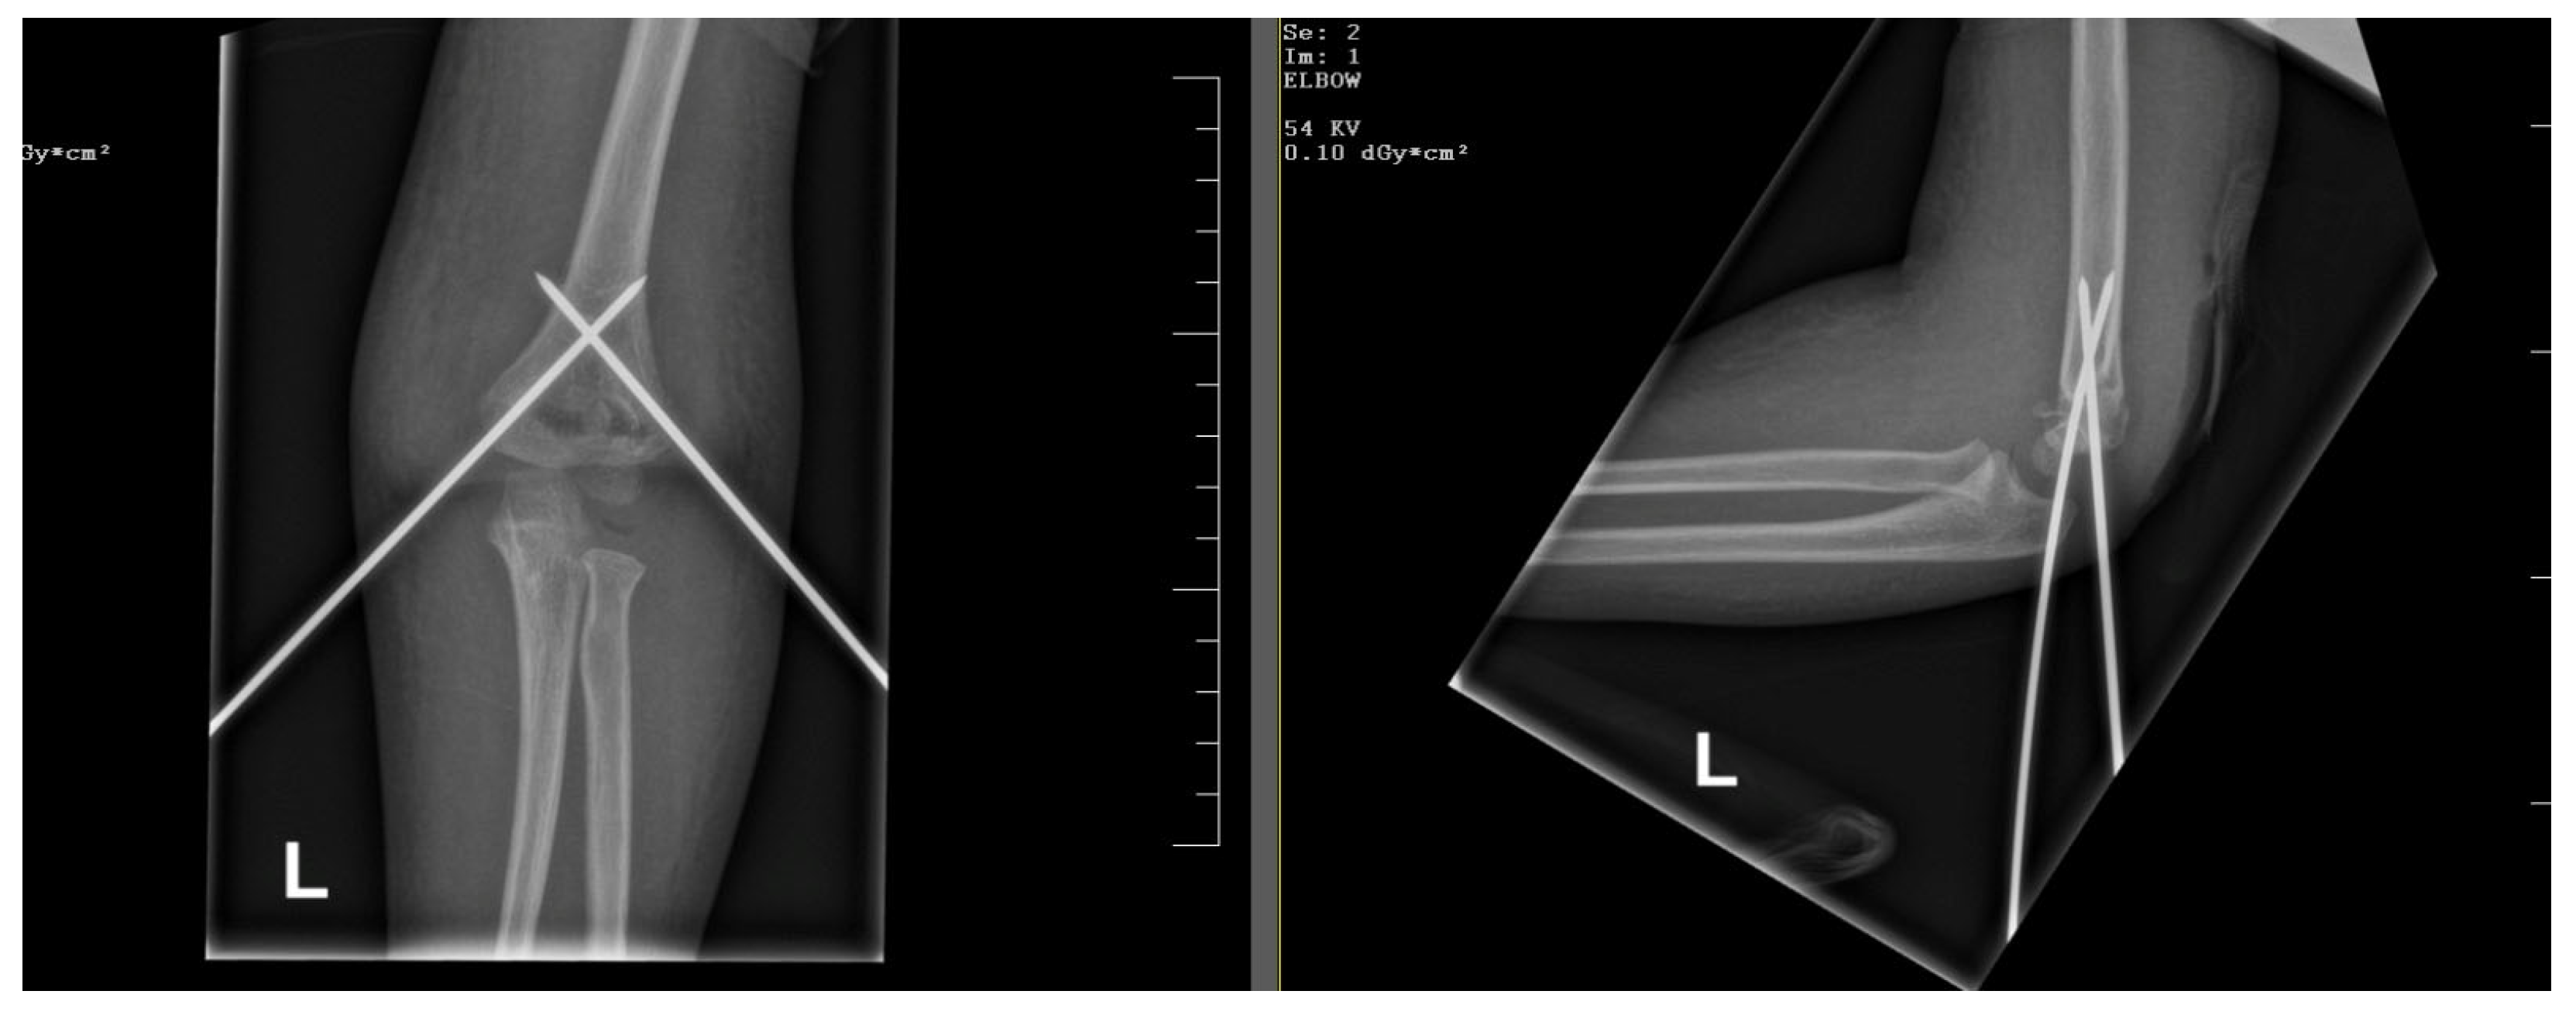

Closed Reduction with Percutaneous Kirschner-Wire Pinning